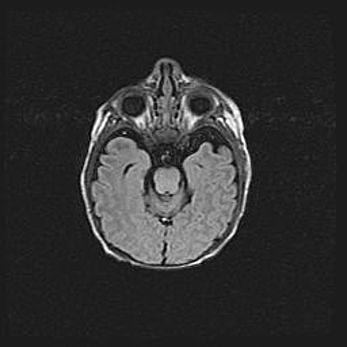

Лейкомаляция с кистозно-глиозной дегенерацией головного мозга.

Возраст: 2 месяца 25 дней

Вес: 6400 г

Окружность головы: 40 см

Срок гестации: 41 неделя

Лейкомаляцию относят к ишемически-гипоксическим повреждениям головного мозга, диагностируемым у новорожденных. При лейкомаляции в головном мозге обнаруживают очаги некроза, возникшие после тяжелой гипоксии и нарушения кровотока. В процессе морфогенеза очаги проходят три стадии: 1) развития некроза, 2) резорбции и 3) формирования глиозного рубца или кисты. Перивентрикулярная лейкомаляция (ПЛ) встречается примерно в 12% случаев среди новорожденных, обычно – у недоношенных детей, причем, частота ее зависит от массы, с которой младенец появился на свет. Наибольшее число малышей страдает лейкомаляцией, если масса при рождении 1500-2500 г.